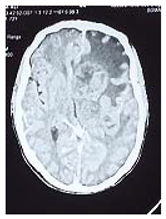

Preprints 114904 i003

Consequent to resuscitation, and clear counseling to the family, the patient prepared for surgical decompression.

Operation: through Rt par median sub occipital craniectomy, macroscopic excision of the tumor was done. The tumor was lobulated well circumscribed, less vascular and extending to the cistern magna.

Patient showed good recovery after the completion of surgery, taken to the ICU on nasal oxygen, and 48 hours released to the general word.

Histopathology

Revealed brain tuberclomata ( extra pulmonary tuberculosis)

Patient was put on anti-tuberculosis according to the program.

In the 7th day post operative, the patient developed high grade fever with respiratory distress, the diagnosis of pneumonia was made and eventually intravenous antibiotic was given, unfortunately, 3 days following he developed Rt lower limb cellulites that complicated with shortness of breath and emergency intubation was done and put on mechanical ventilation but few hours following he died.